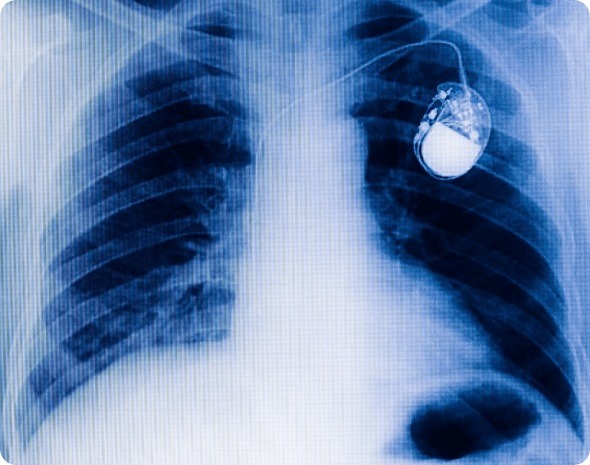

Traditional chest pacemaker one x-ray film.

Pacemakers have been around for a very long time, they're great devices, critical for many people who have slow heartbeats. While they're very effective, they have some issues. There are two main aspects relating to these issues.

One is the surgical procedure to place the device. You have to make an incision in the upper chest to get the device underneath the skin. Second, in order to deliver the energy to the heart muscle there's a wire that connects this generator under the skin to the heart muscle itself.

There are several problems with that wire, it can fracture over time or become incorporated into the healing tissue around the wire causing scar tissue to build up.

If the wire has to be removed because of fracture or infection, removing it can be a complicated thing. Lead extraction can have some disastrous consequences. Most of the time it's okay but sometimes it's not. While the pacemaker has advanced over the past half century, we're still limited by the fact that it has a lead and a generator.